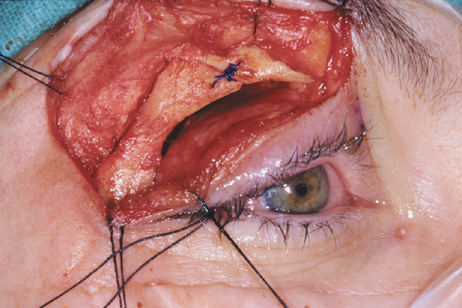

Fig. 6. Lateral orbitotomy through upper eyelid skin crease A. Photo demonstrating right globe ptosis present for more than 2 years. B. Axial CT scan showing a well outlined oval lesion in the lacrimal gland

fossa. C. Coronal CT showing lesion pushing globe inferiorly. D. Skin crease excision marked for lateral orbitotomy. E. Lateral orbital rim exposed. Bone cuts made above frontozygomatic suture

and at zygomatic arch. F. Lateral wall removed. Subperiosteal space exposed. Hard tumor could be

palpated in area of lacrimal gland. G. Benign mixed tumor of lacrimal gland removed. H. Bone sutured into place. I. Skin crease closed. |